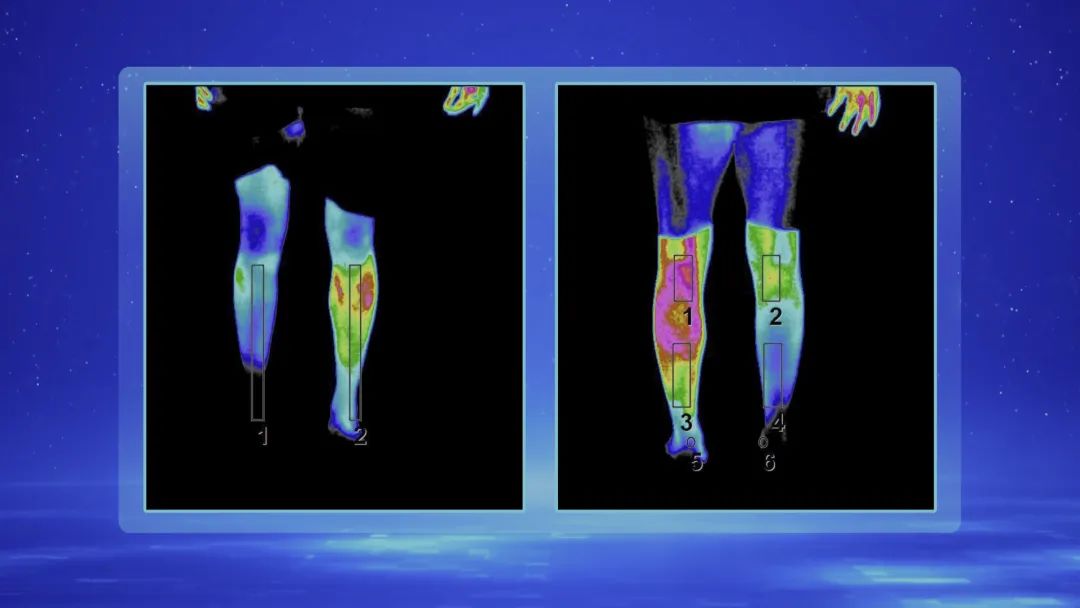

糖尿病多年的患者,右腿冰凉,更要命的是每天24小时的下肢疼痛,让他痛不欲生,多次请求大夫帮助把腿锯掉!他的下肢血管真的堵塞那么严重吗?我们从他的腿部红外成像上,已经看不到他的脚!专家指出:这种情况很危险,如果不能尽快想出办法,截肢是必然的结果!那么,今天的专家,会给我们带来惊喜吗?更多详情,请关注宣武医院神经外科神经脊柱中心朱宏伟主任为您带来的《跨界拯救濒危的血管》。